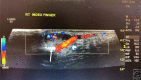

Masson's Tumor of the Finger

Keywords: Masson's tumor; finger; hand mass; intravascular papillary endothelial hyperplasia; organizing thrombus.